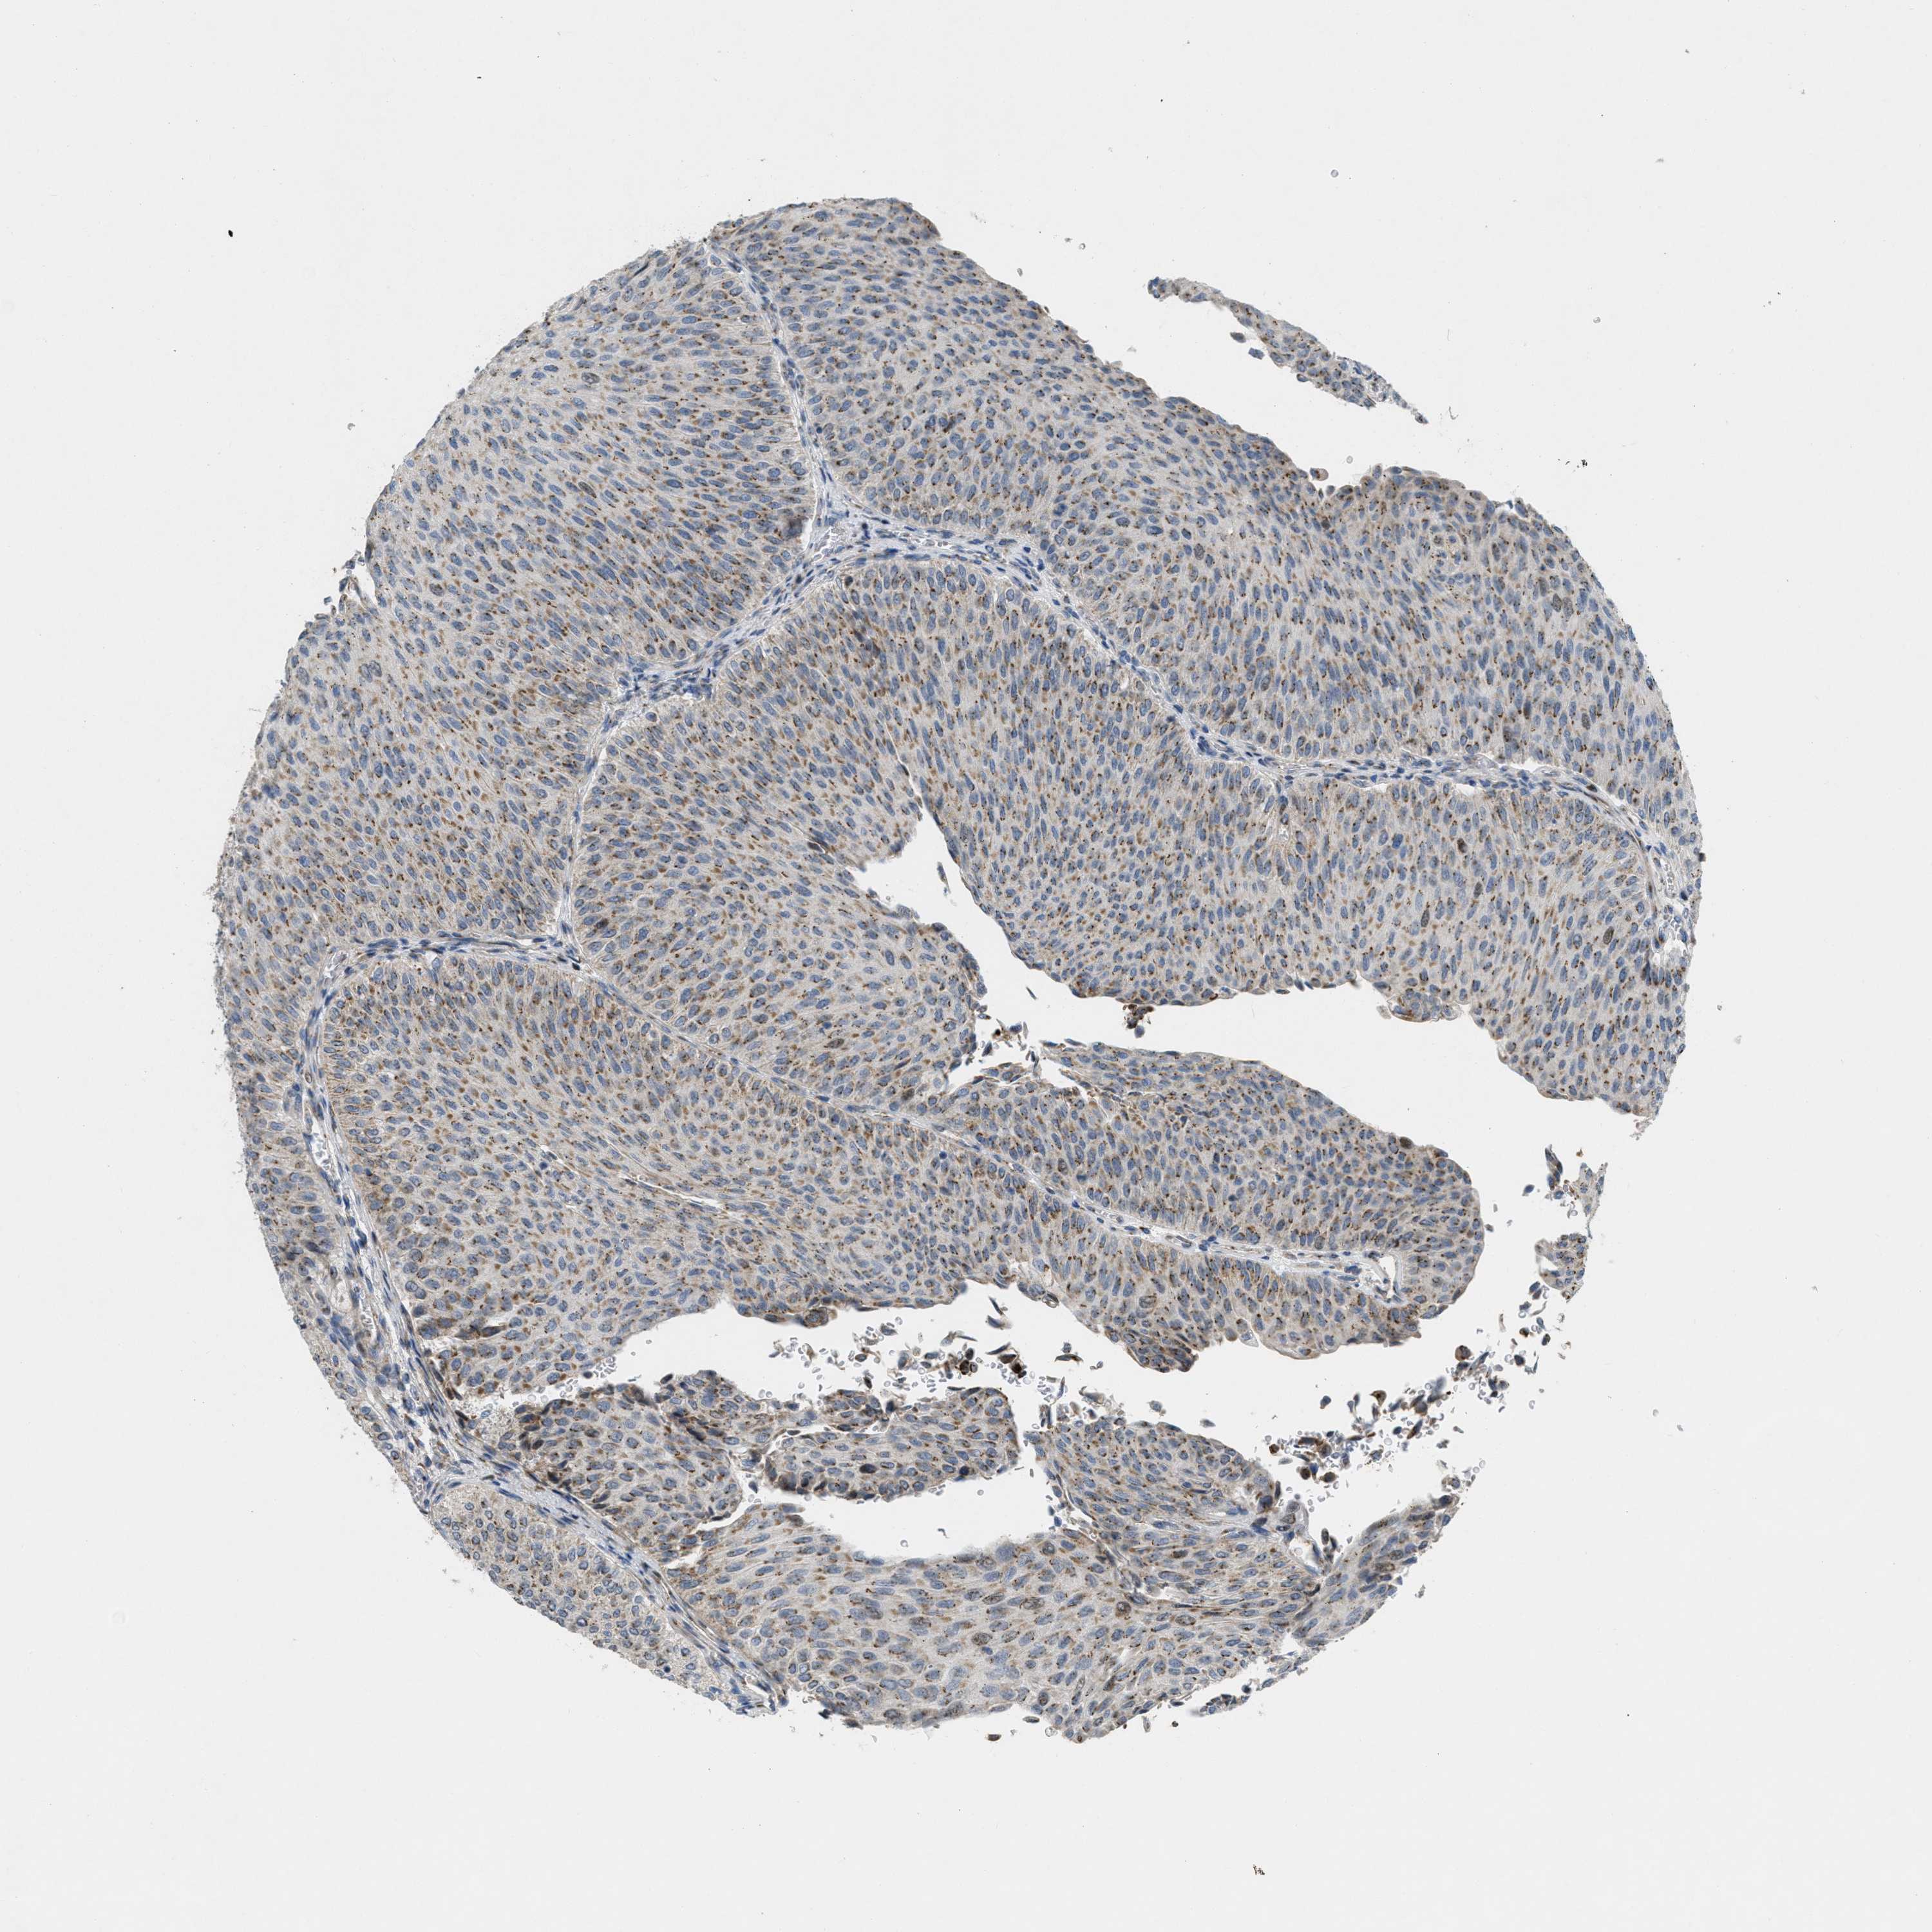

UROTHELIAL CANCER - Protein expressioni

A mouse-over function shows sample information and annotation data. Click on an image to view it in a full screen mode. Samples can be filtered based on level of antibody staining by selecting one or several of the following categories: high, medium, low and not detected. The assay and annotation is described here.

Note that samples used for immunohistochemistry by the Human Protein Atlas do not correspond to samples in the TCGA dataset.

Antibody stainingi

Antibody staining in the annotated cell types in the current human tissue is reported as not detected, low, medium, or high, based on conventional immunohistochemistry profiling in selected tissues. This score is based on the combination of the staining intensity and fraction of stained cells.

Each image is clickable and will lead to virtual microscopy that enables deeper exploration of all samples and also displays staining intensity scores, fraction scores and subcellular localization as well as patient and tissue information for each sample.

Antibody HPA014909

Antibody HPA017347

Staining

High

Medium

Low

Not detected

Intensity

Strong

Moderate

Weak

Negative

Quantity

>75%

75%-25%

<25%

None

Location

Nuclear

Cytoplasmic/membranous

Cytoplasmic/membranous,nuclear

Urothelial carcinoma, Low grade

Urothelial carcinoma, High grade